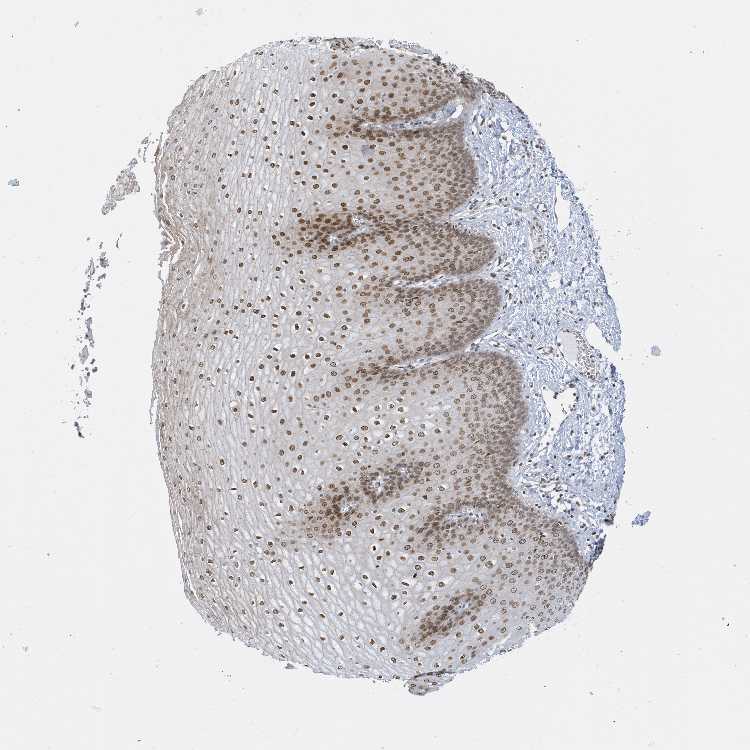

ESOPHAGUS - Antibody stainingi

Antibody staining in the annotated cell types in the current human tissue is reported as not detected, low, medium, or high, based on conventional immunohistochemistry profiling in selected tissues. This score is based on the combination of the staining intensity and fraction of stained cells.

Each image is clickable and will lead to virtual microscopy that enables deeper exploration of all samples and also displays staining intensity scores, fraction scores and subcellular localization as well as patient and tissue information for each sample.

Antibody HPA035428

Squamous epithelial cells High